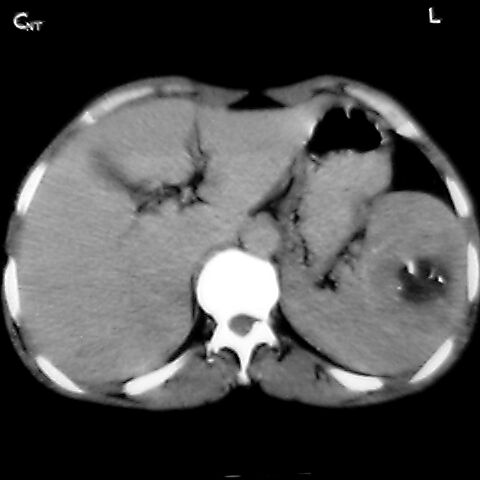

女 48岁 食道癌术前体检发现脾占位。

脾胀内部巨大低密度肿块,边界清或不清,中心坏死,轻度增强,内见散在钙化,结合食道癌病史多考虑:转移癌.

1肝右下叶小囊肿2右肾上极囊肿或错构瘤3脾脏不典型血管瘤可能性大.

脾脏低密度灶伴钙化,增强化明显,中心见液化坏死灶,强化延时明显。考虑血管瘤。转移瘤待排。

右肾见类圆形低密度影.结合病史.脾及右肾转移性ca可能性大